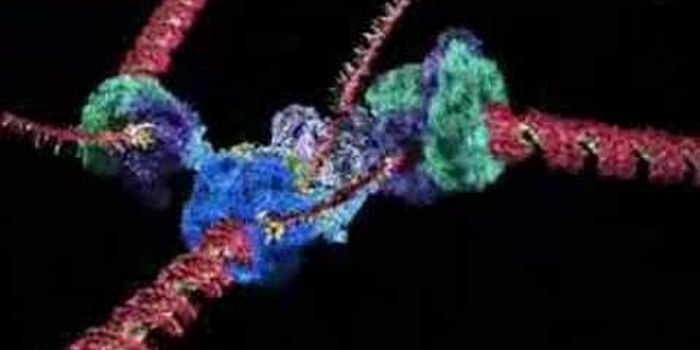

SEP 25, 2017VideosThe Koch Institute at MIT presents awards for amazing microscopy images. One winner, "Mind the Gap," is seen here. The i ...